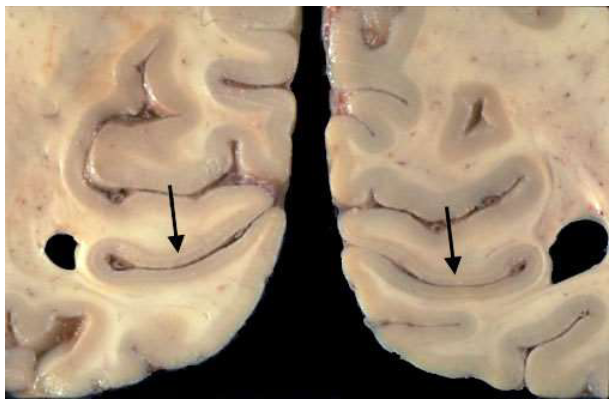

van stippen naar strepen: nucleus geniculatus lateralis (LGN) → structuur

6-lagige structuur, in het midden gebogen

neuronen in onderste 2 lagen zijn fysiek groter dan die in bovenste 4 lagen

onderste 2 lagen → magnocellulaire lagen

ontvangen input van M-ganglioncellen in netvlies

bovenste 4 lagen → parvocellulaire lagen

ontvangen input van P-ganglioncellen

magno- & parvocellulaire lagen: van elkaar gescheiden door koniocellulaire lagen

betrokken bij doorgeven van signalen van S-kegeltjes

kunnen deel uitmaken van primordiale blauw-gele pathway